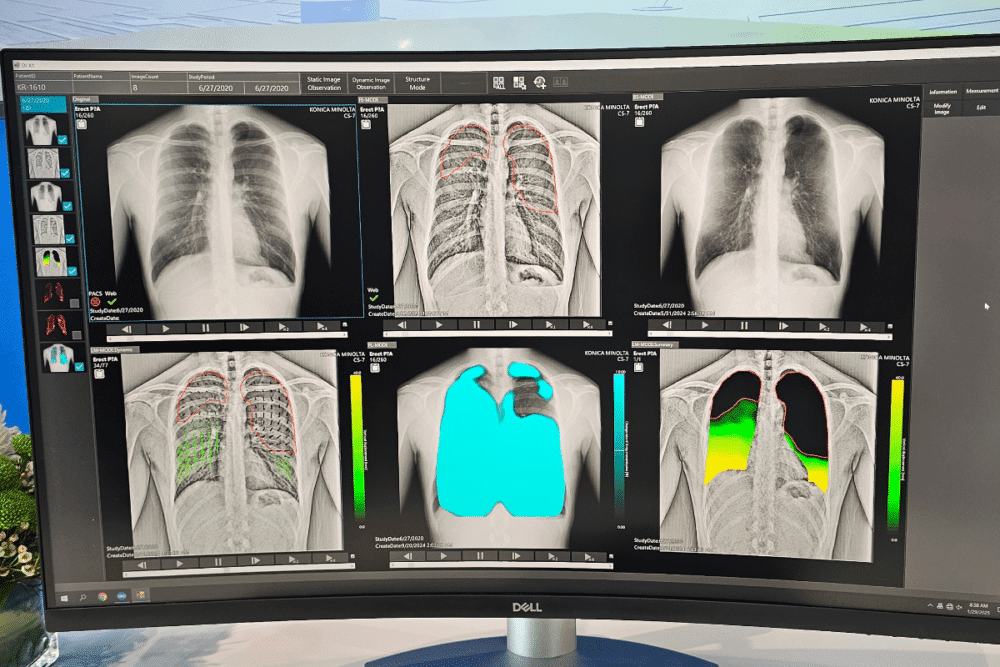

Mário Garcia: “Dynamic imaging provides crucial insights that static imaging cannot. For instance, it helps determine whether a pacemaker catheter is correctly positioned, ensuring its proper placement. Additionally, it plays a key role in assessing lung function by evaluating the patient’s breathing capacity. While a static image may suggest that everything appears normal, dynamic imaging reveals whether the lungs are functioning correctly and if the patient is breathing properly. This system therefore enables radiologists to detect new diagnostic insights that were not previously possible with static imaging. New software tools with AI are being developed and incorporated in our Dynamic Radiography technology.”

Mário Garcia: “The dynamic images are analyzed using artificial intelligence. From these images, different diagnostic views can be generated, helping assess lung function, areas of reduced capacity, and abnormalities. For example, in one acquisition, green areas may indicate missing lung capacity. Another image can provide lung measurements and breathing assessments, etc.”